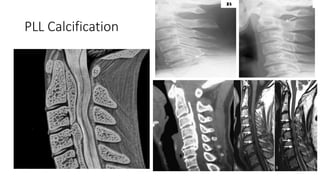

PLL Calcification

PLL